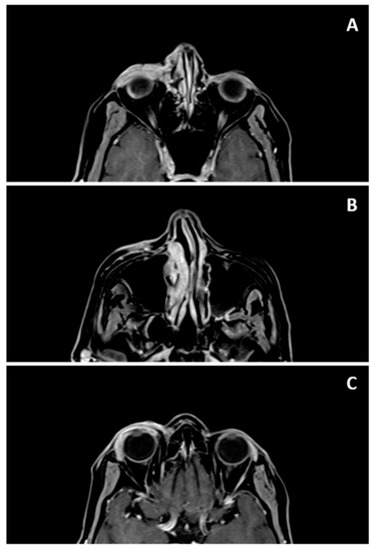

2.1. Case Report